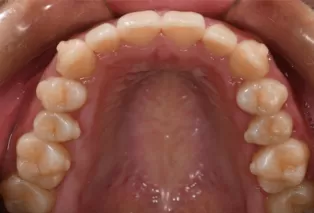

Intraoral photos